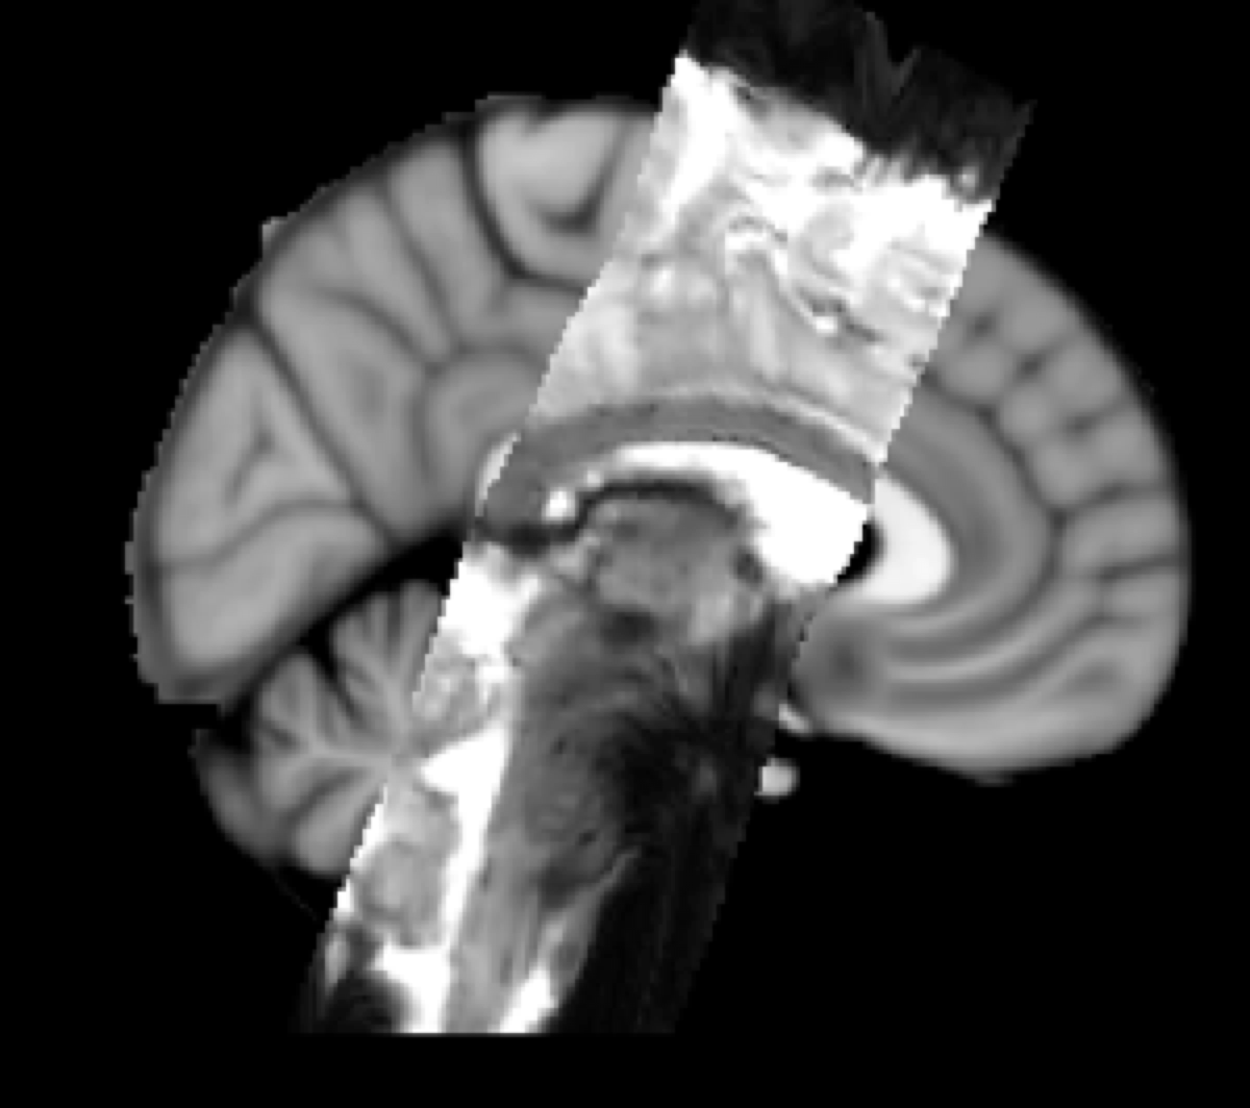

Example result: Three-stage registration - Partial FOV EPI to Whole-brain EPI to T1 Structural to Standard Space

Example of Three Stage Registration